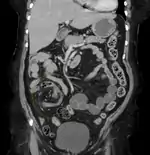

CT scan of a small bowel volvulus. It shows two juxtaposed segments of narrowing, which is the spot of mesentery rotation. The other signs indicate strangulation.

CT scan of a cecal volvulus